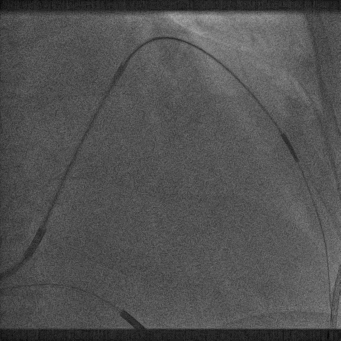

最终影像

● 保留PTCA导丝,透视下回撤鞘管出冠状静脉口至心房内;

● 撤除PTCA钢丝,换做LV导线的直钢丝至右心房中下部;

● 切鞘前调整电极张力

● 切开鞘管:卡住电极,固定刀片侧手,先切开止血阀,然后外撤鞘管,一气呵成,不要停顿。

➛ 撤出鞘中鞘后调整导线弧度,弧度过多,容易脱位,适当的弧度是保证撤鞘时导线稳定的前提